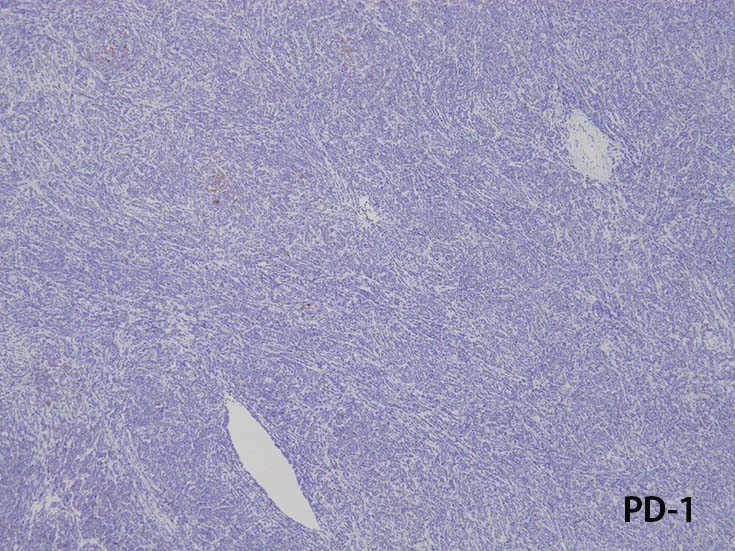

c-KIT(CD117)

- まれにc-KIT(CD117)+; FLT3の活性化変異に関連する.